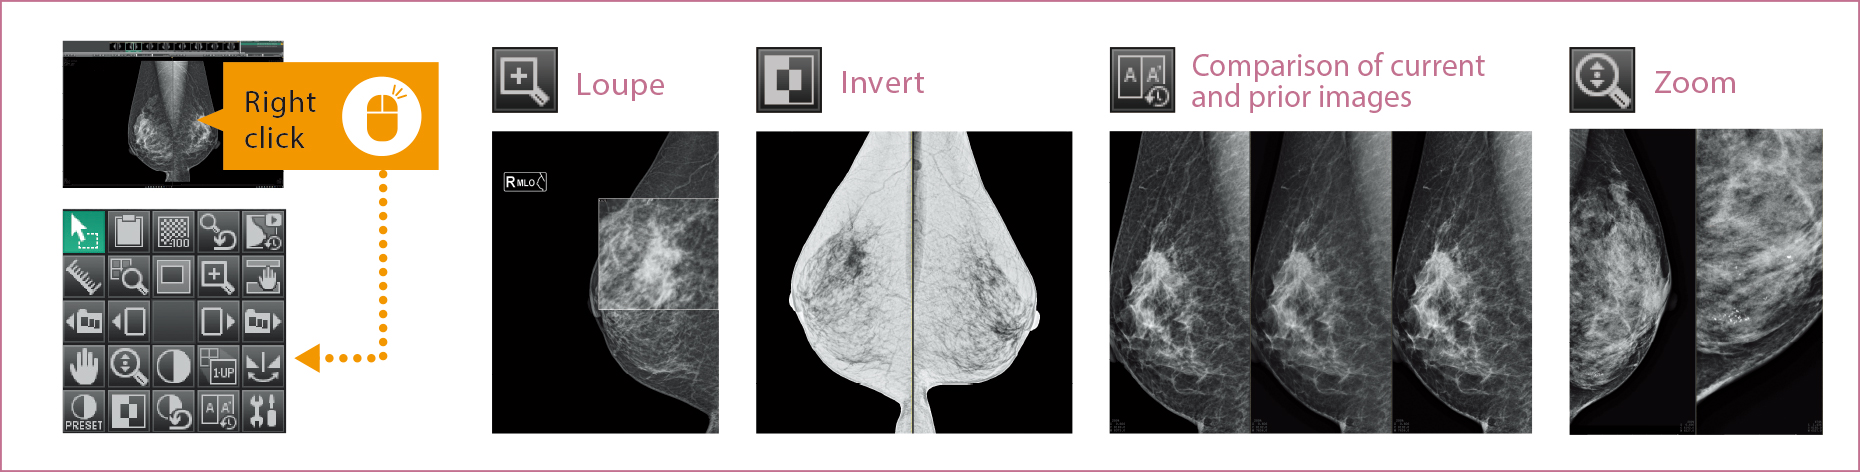

Respalda el trabajo de los usuarios que realizan diagnósticos con protocolos de lectura adaptados al diagnóstico mamográfico y visualizaciones de imágenes sin interrupciones. La personalización de protocolos de lectura incluye la configuración para realizar comparaciones de imágenes actuales y anteriores así como para las vistas sintetizadas S-view a partir de imágenes de tomosíntesis de AMULET Innovality y AMULET SOPHINITY.

La ventana de miniaturas permite a los usuarios ver instantáneamente todas las imágenes tomadas para cada examen individual en una sola vista. Cada imagen puede seleccionarse y mostrarse fácilmente arrastrando y soltando.